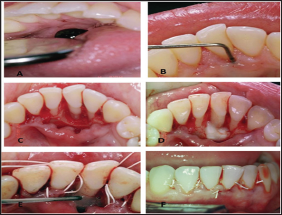

Figure 1: A: The lower metal ball of the tongue piercing came in contact with area where the destruction of the lingual alveolar plate was present.

B: 8 mm pocket depth (PD) on the lingual surface of # 41.

C: Full thickness flaps raised, Lingual plate was missing.

D: EDTA was cautiously placed on the root surface for two minutes.

E: Emdogain® was placed on the surface of the root of # 41.

F: Flaps were sutured back.

A 26-year-old woman came in our office complaining of gum bleeding and swelling. Intraoral examination revealed a tongue piercing and also gum swelling in the lingual area of the lower central incisors and an 8 mm pocket depth (PD) on the lingual surface of # 41 (Figure 1). Radiographic examination showed distraction of the lingual plate in the area of # 31 and # 41. It was also noted that the lower metal ball of the tongue piercing came in contact with area where the destruction of the lingual alveolar plate was present (Figure 1). After explaining to the patient the problems that where created due to the tongue piercing, it was advised to her to remove the tongue jewel in order to begin periodontal treatment in the area. The goal of the treatment was to reduce inflammation and increase the clinical attachment level (CAL).

Conservative periodontal treatment (scaling and root planning) was performed. After one month there was reduction of inflammation but no reduction of PD was noted. At the surgical treatment a full thickness flap was performed at the area of # 31 - 41. Granulation tissue and residual calculus were removed from the area. Then, EDTA was cautiously placed on the root surface for two minutes, which was then removed by irrigating saline at the site (Figure 1). After the irrigation the root was dried and then carefully Emdogain was placed on the surface of the root of # 41 (Figure 1). Finally, the flap was sutured back using resorbable sutures (Figure1). The patient was given post-operative instructions and medication was administered (amoxicillin 500 mg every 8 hours, ibuprofen every 6 hours and chlorhexidine 0.12%). Sutures were removed after 2 weeks. After 6 months, a 6 mm reduction of the pocket depth, increased CAL and no inflammation was observed in the area (Figure 2). Comparison of radiographs before and after surgical treatment confirms the results (Figure 2).